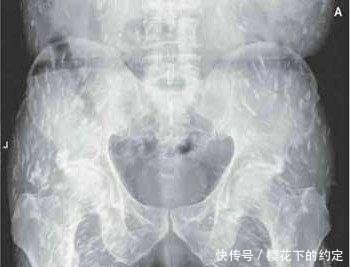

通过检查医生发现,婷婷的大脑里也有囊虫钙化现象。“这表示已有囊虫死去,说明囊虫感染的时间已经比较长。而且患者眼球突出,视网膜出血,全身多处感染,还伴有癫痫发作。”省一院神经内科主任医师孟强教授说,这么严重的囊虫感染,他也是第一次遇到。

根据囊尾蚴寄生部位的不同,分为脑囊尾蚴病、眼囊尾蚴病、皮肌型囊尾蚴病等,其中以寄生在脑组织者最严重。